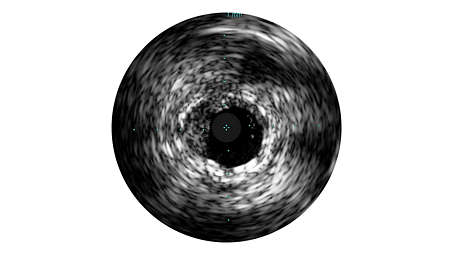

IVUS imaging helps physicians assess disease markers including plaque burden percentage, lesion location and morphology, calcium volume, and the presence of thrombus. It also enables analysis of crucial parameters – like luminal cross-sectional measurements – and helps aid in disease diagnosis. Grayscale enhances procedures

Grayscale enhances angiography procedures by enabling detailed views. Angiography produces a shadowgram of contrast, while IVUS visualizes extent and location of plaque, enabling precise disease assessment, vessel and optimal stent placement. IVUS guidance has been associated with a 74% change in PCI strategy and reduced MACE, MI, TLR, and death in large studies.¹, ²